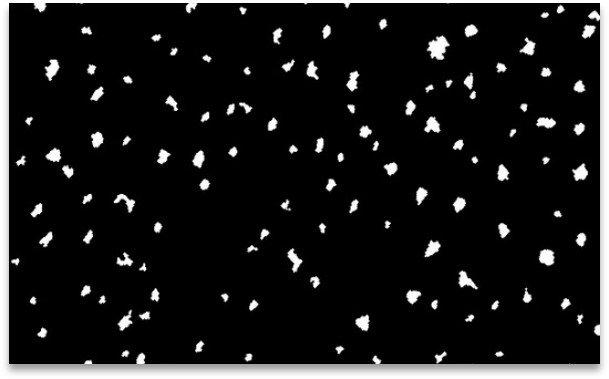

La couleur de la zone d’échantillonnage est grise et uniforme, de manière à distinguer clairement les taches de sébum foncées. Les échantillons prélevés sur ces patchs sont analysés avec le lecteur d’échantillons Pixience et la caméra C-Cube de manière standardisée et systématique. L’analyse des niveaux d’intensité dans la zone de l’échantillon permet de déterminer un seuil entre le « fond » (la zone grise de l’échantillon) et l’intensité de la lumière « forme » (la zone noire, c’est-à-dire le sébum).

Il est ainsi facile de les distinguer et de mesurer la surface relative de sébum par rapport à la surface totale de la tache (exprimée en pourcentage de la surface totale).